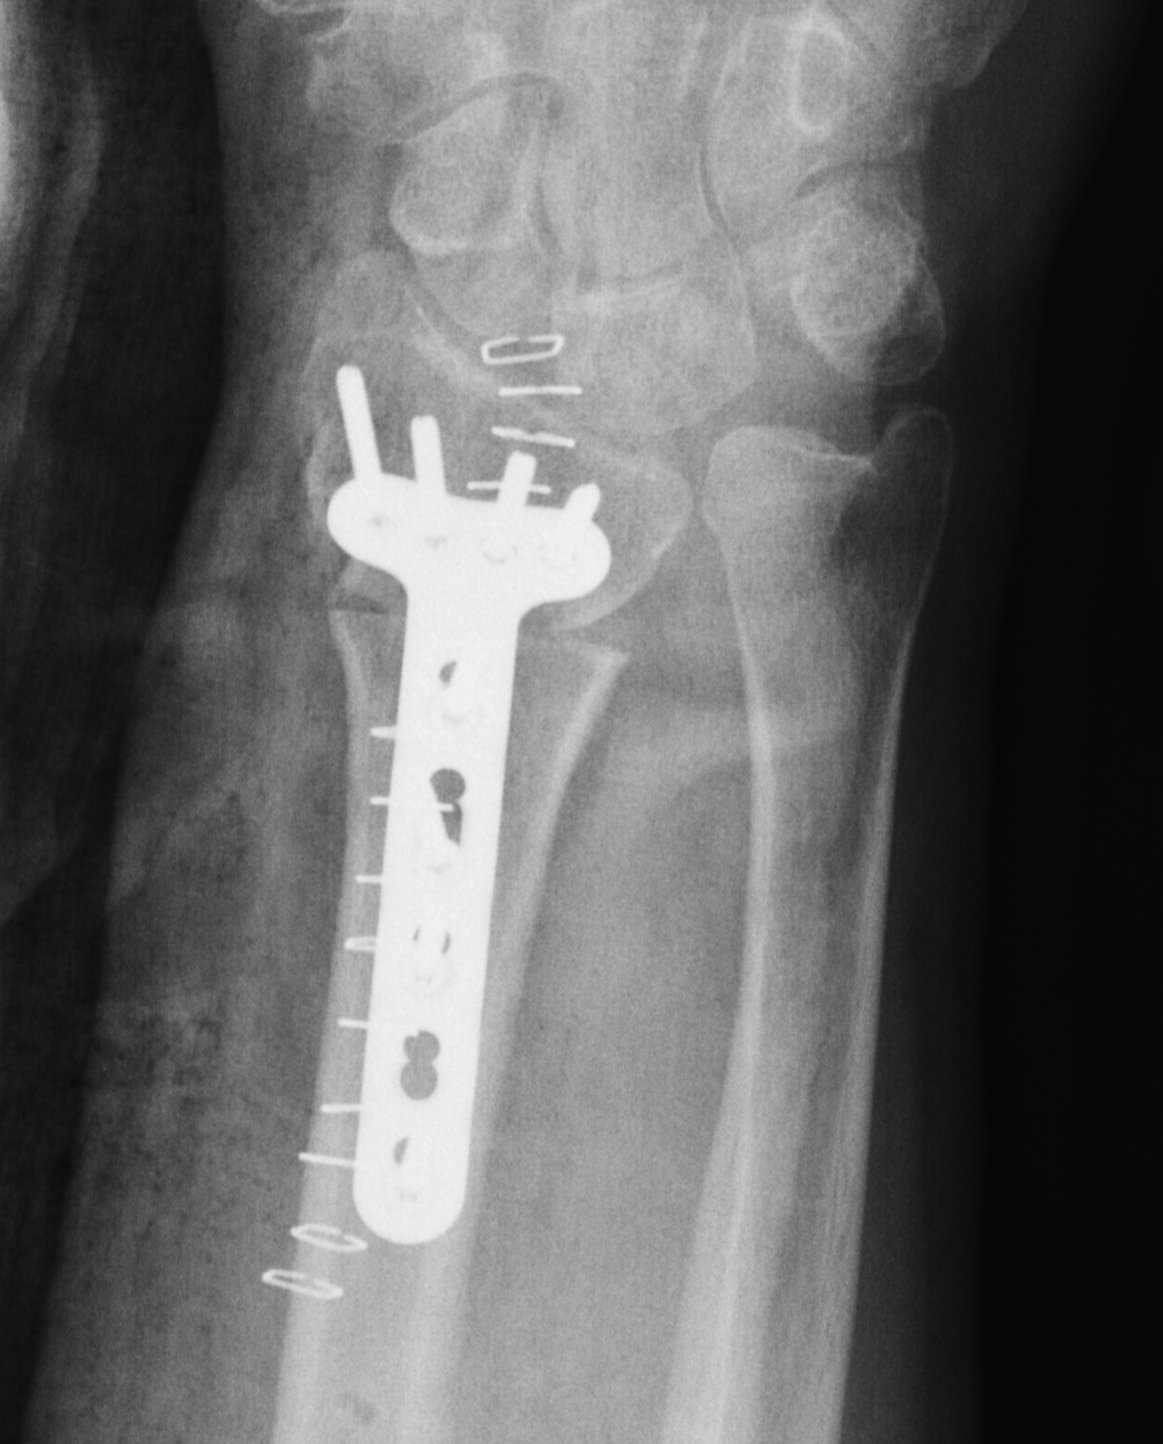

Volar opening wedge

Radial Malunion Volar Opening Wedge OsteotomyRadial Malunion Volar Opening Wedge Osteotomy Lateral

Advantage

Volar approach and plate

Disadvantage

May require dorsal approach to bone graft

Technique

Bed of FCR approach

- release brachioradialis

- protect structures with retractors

- perform osteotomy parallel to articular surface

- sufficient distal bone for screw fixation

- correct distal radius in two planes

- apply volar plate

- bone graft defect through radial aspect of wound

+/- dorsal approach to insert bone graft

Volar osteotomyVolar osteotomyvolar osteotomyvolar osteotomy